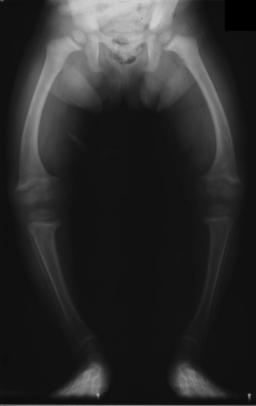

구루병은 비타민 D, 칼슘, 인의 결핍으로 인해 뼈의 무기질 침착이 제대로 이루어지지 않아 발생하는 질환이다. 주요 원인으로는 비타민 D 섭취 부족, 햇빛 노출 부족, 선천성 대사 장애 등이 있으며, 모체의 비타민 D 결핍은 태아에게도 영향을 미칠 수 있다. 증상으로는 뼈의 압통, 골절, 두개골 변형, O자형 다리, 척추 측만증 등이 나타날 수 있으며, 혈액 검사, 골밀도 검사, 방사선 사진 등을 통해 진단한다. 예방 및 치료를 위해서는 충분한 햇빛 노출, 비타민 D 및 칼슘 섭취가 중요하며, 심한 변형의 경우 수술적 교정이 필요할 수 있다. 2010년대 이후 대한민국에서는 자외선 기피, 모유 수유, 알레르기 질환 대책 등으로 인해 구루병 발생이 증가하는 경향을 보이고 있다.

어린아이는 O다리와 두꺼워진 발목과 손목이 있을 수 있으며,[17] 나이가 많은 아이는 안짱다리가 있을 수 있다.[14] 척추 측만증 또는 요추 척추전만증의 척추 만곡이 나타날 수 있다. 골반뼈가 변형될 수 있다. 구루병 염주는 늑골연골관절에 형성되는 결절로 인한 두꺼워짐으로 인해 발생할 수 있다. 이는 몸의 양쪽에 선을 따라 각 늑골의 중앙에 보이는 혹으로 나타나며, 묵주와 비슷하여 그 이름이 붙었다. 비둘기 가슴[14]의 변형으로 해리슨의 홈이 나타날 수 있다.

X선 또는 방사선 사진은 구루병의 고전적인 양상(O다리, 변형된 가슴)을 보여준다. 두개골의 변화도 발생하여 "사각형 머리" 모양인 "사각두"가 나타난다.[18] 이러한 변형은 치료하지 않으면 성인기에도 지속된다. 장기적인 결과로는 장골의 영구적인 만곡 또는 변형과 굽은 등이 있다.[19]